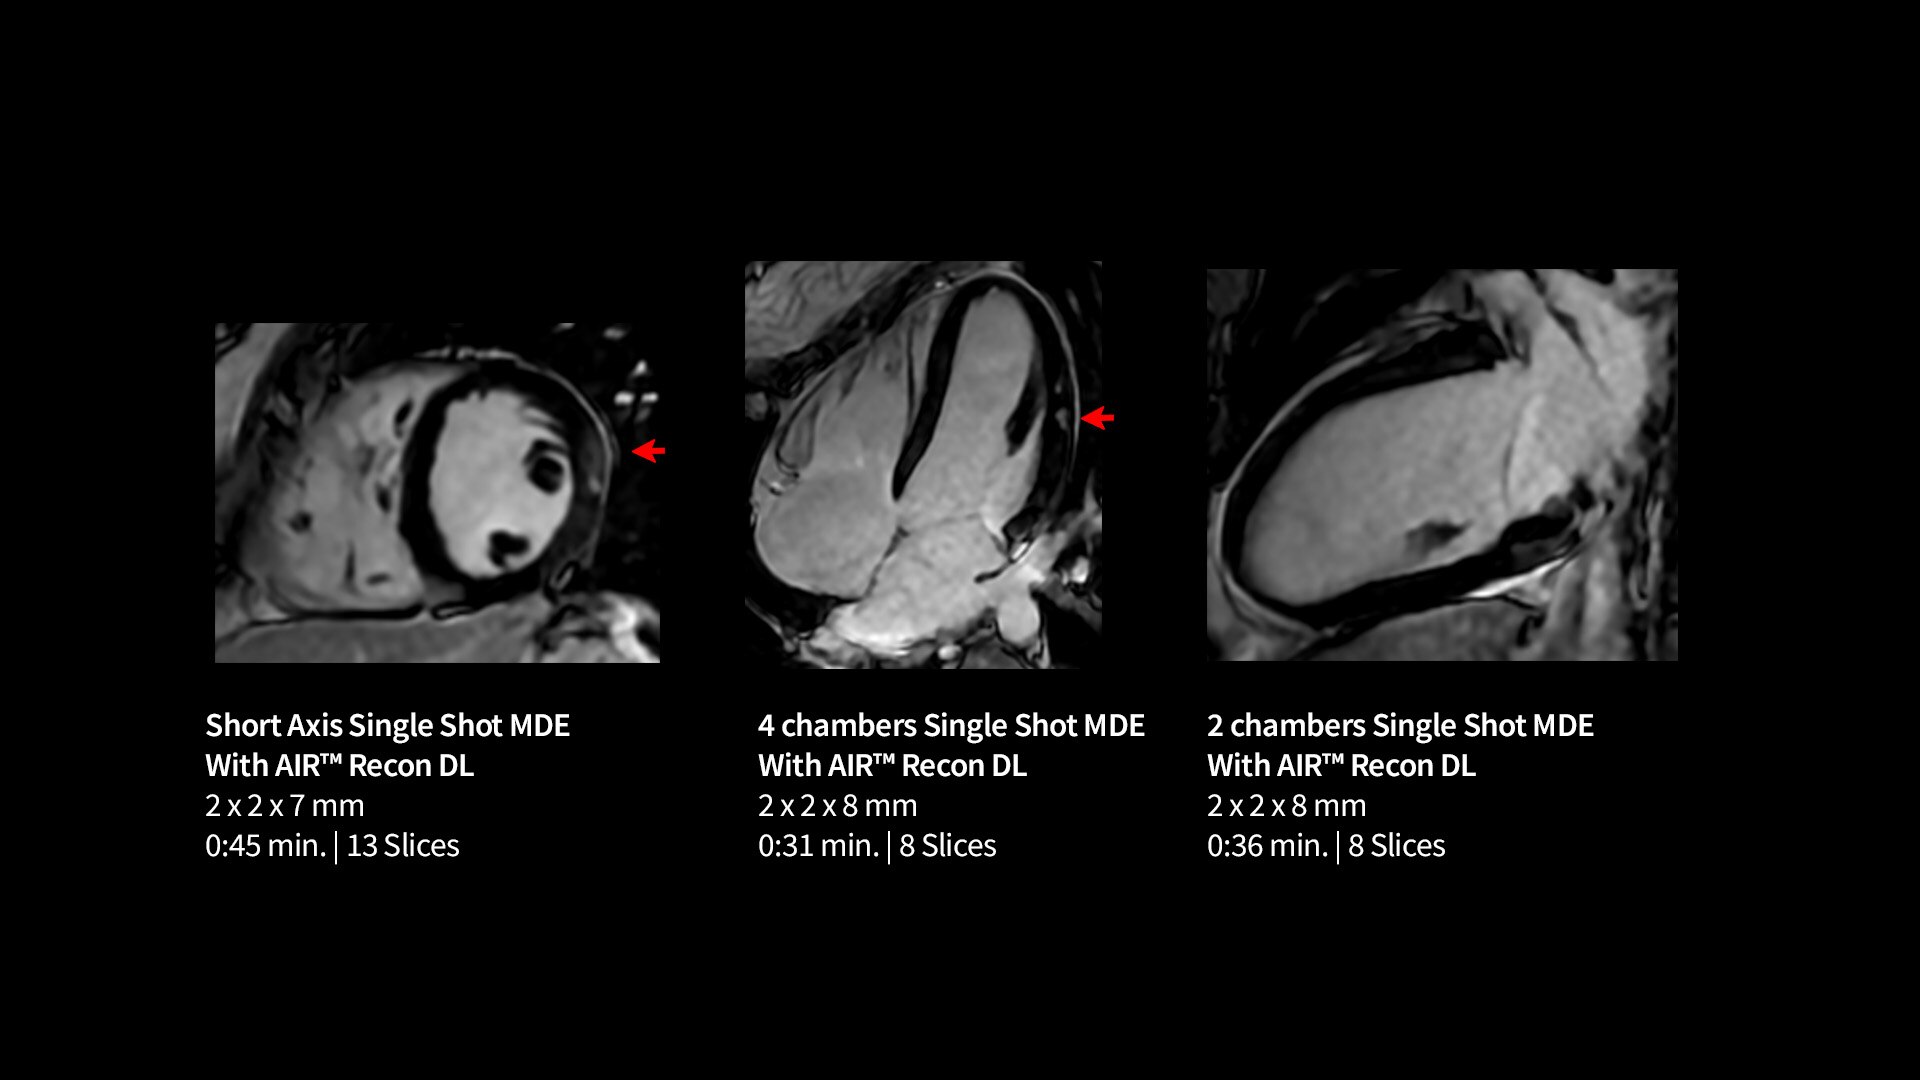

Capture clarity

Improve SNR and image sharpness by up to 60% with AIR™ Recon DL

Life-Speed imaging

Achieve up to 12X acceleration and up to 83% scan time reduction*